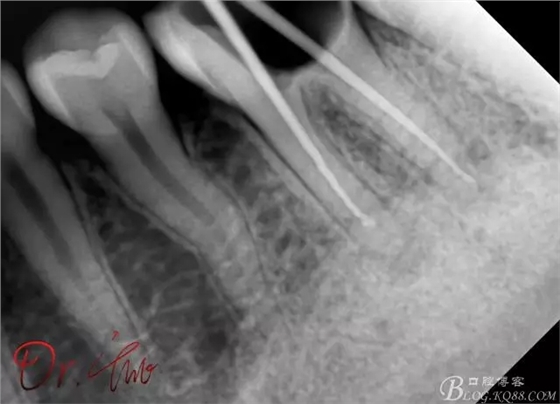

重點第二例病例,初診

拍片確定長度

試主尖,近中頰側(cè)形成臺階

試主尖,近中頰側(cè)再次拍片查看臺階位置及確定長度

試主尖,近中頰側(cè)試主尖,此時手用銼02錐度的已擴到30號,可以明顯感覺到臺階位置,挫預(yù)彎后找好正確位置可順利到達根尖,但是機用銼就是下不去,也是郁悶

試主尖,在30號02錐度K挫到達根尖后,用02錐度牙膠尖找準位置,進行試尖

最后根充,明顯可看到臺階位置,期待預(yù)后效果